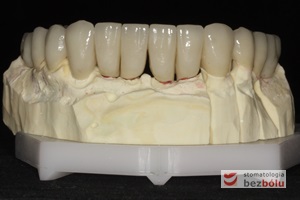

Gotowa praca protetyczna - korony cerkonowo-ceramiczne na modelu roboczym dostarczone z laboratorium protetycznego

Gotowa praca protetyczna – korony cerkonowo-ceramiczne na modelu roboczym dostarczone z laboratorium protetycznego